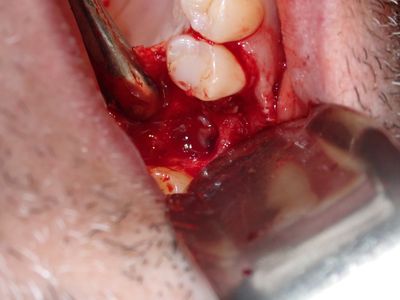

PWong - remove impl 26 and graft

implant placed 4 months ago in 4-5mm height of bone, no sinus lifting procedure, loose, removed implant with forcep, flapped region, large sinus communication, about 6mm+ diameter, likely larger, placed fibrin membrane followed by collagen membrane soaked in prf fluid at floor of sinus, membrane oversized, borders in internal aspect of defect, packed defect with sticky bone from 50/50 allograft, additional collagen membrane and fibrin membrane over crest